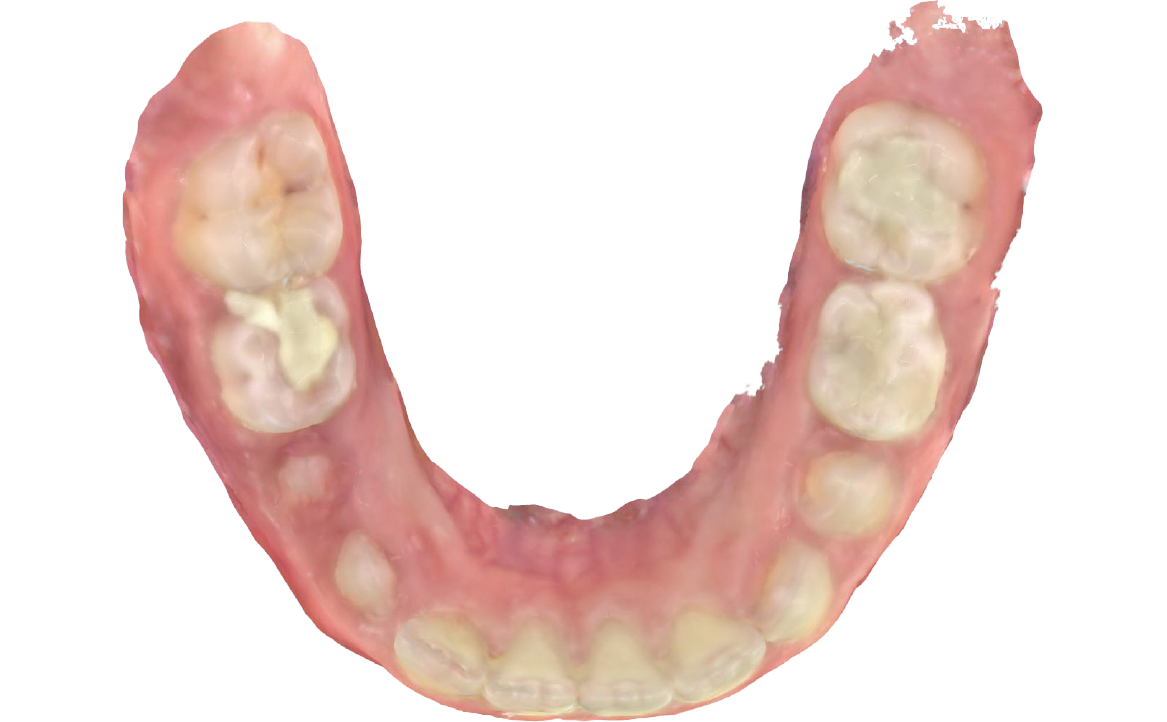

L’overjet e l’overbite sono entrambi ridotti in massima intercuspidazione. Trasversalmente il mascellare superiore è contratto (fig. 4-7).

Fig. 7A Foto dell'arcata inferiore.